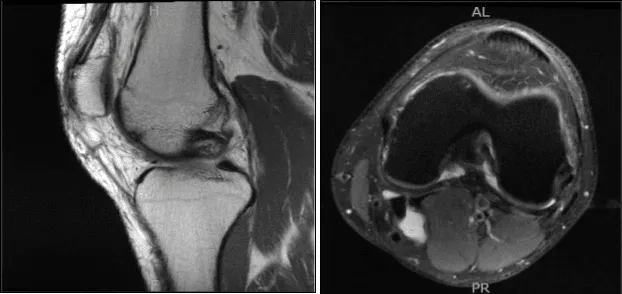

MRI results were presented today and showed lateral meniscal tear. Mild partial-thickness cartilage loss along the central trochlear groove and in the lateral compartment. Trace left knee joint effusion and small Baker’s cyst.

MRI-3T Left Knee Non-contrast